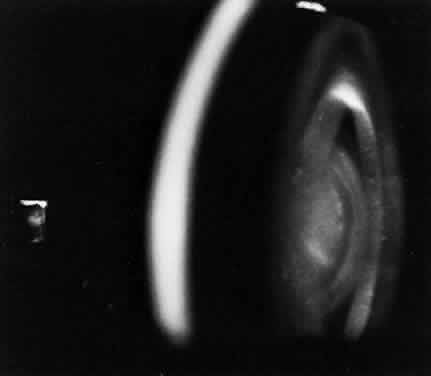

Corneal clouding is a prominent manifestation of the Scheie syndrome (Fig. 10).168 Developing early in life, sometimes present at birth, the corneal clouding tends to worsen with age and may ultimately interfere with vision. The corneal involvement is diffuse but tends to be densest peripherally. Clinically, the hazy cornea may appear enlarged, edematous, and thickened, initially raising suspicion of glaucoma, particularly when telltale somatic signs of mucopolysaccharidosis are minimal. The pathologic corneal changes are similar to those in Hurler syndrome.168,176 Corneal transplants have been tried but with little success. In most cases reported, the ocular pressure has been normal or in the upper range of normal, but in some cases glaucoma has been documented.177,178

Fig. 10. Corneal clouding in MPS IS. (Courtesy James J. Reidy, MD)